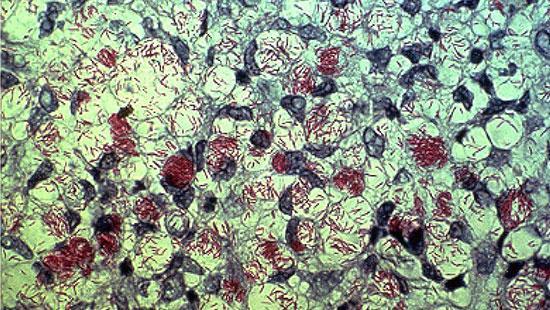

28ژانویه هر سال (مصادف با هشتم بهمن ماه) روز جهانی جذام نام گذاری شده است. این بیماری را جزو بیماری های میکروبی عفونی پوستی (مایکو باکتریوم لپره) قابل سرایت تقسیم بندی کرده اند .طبق آمار سال 2016 ، حدود 214 هزاربیمار مبتلا به جذام شناسایی شده اند.این بیماری به نام هانسن هم شناخته می شود زیرا این پزشک نروژی توانست میکروب این بیماری را شناسایی کند.

مالتی -باسیلاری

بیمار تعداد بیشتری باسیل در بدن خود داردو ضایعات بدن بیمار بیشتر است .